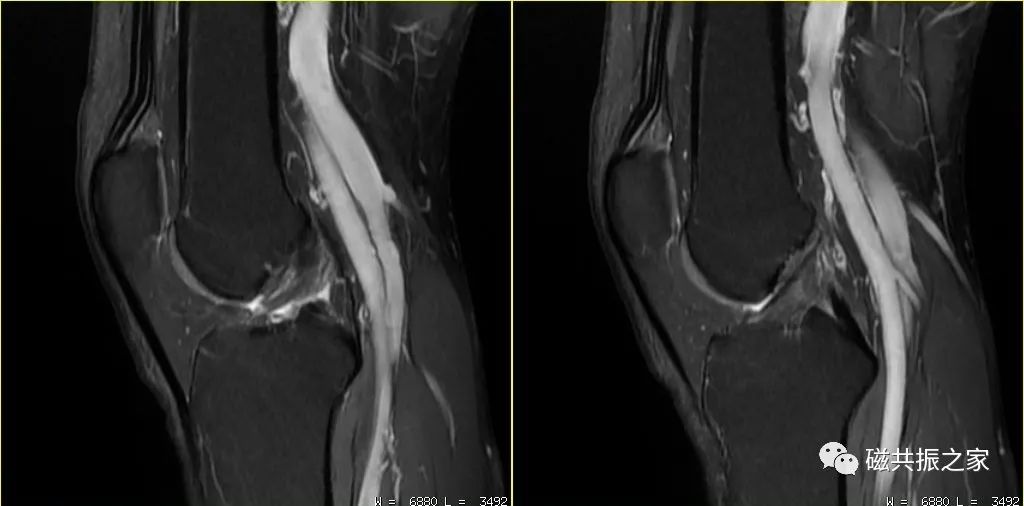

左图:TE 35ms;髌韧带局部区域魔角现象较明显。右图:TE 70ms;无明显魔角现象。

在摆放扫描部位时尽量避免扫描部位与主磁场呈50°-60°夹角,如膝关节、跟腱的扫描。图△膝关节PDWI序列,髌韧带区域的魔角效应得到了明显的改善。